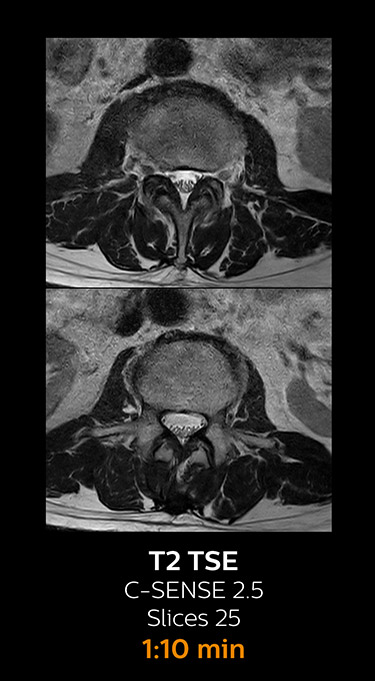

Fast MRI of lumbar spine

which corresponds to 34% reduction.

With Compressed SENSE, the scan time for the routine lumbar spine examination at KNC was reduced from 11:41 to 8:17 minutes,

MRI examination of the lumbar spine with Compressed SENSE

Ingenia 3.0T CX

Scan time 8:17 min. (was 11:41 min. without Compressed SENSE)